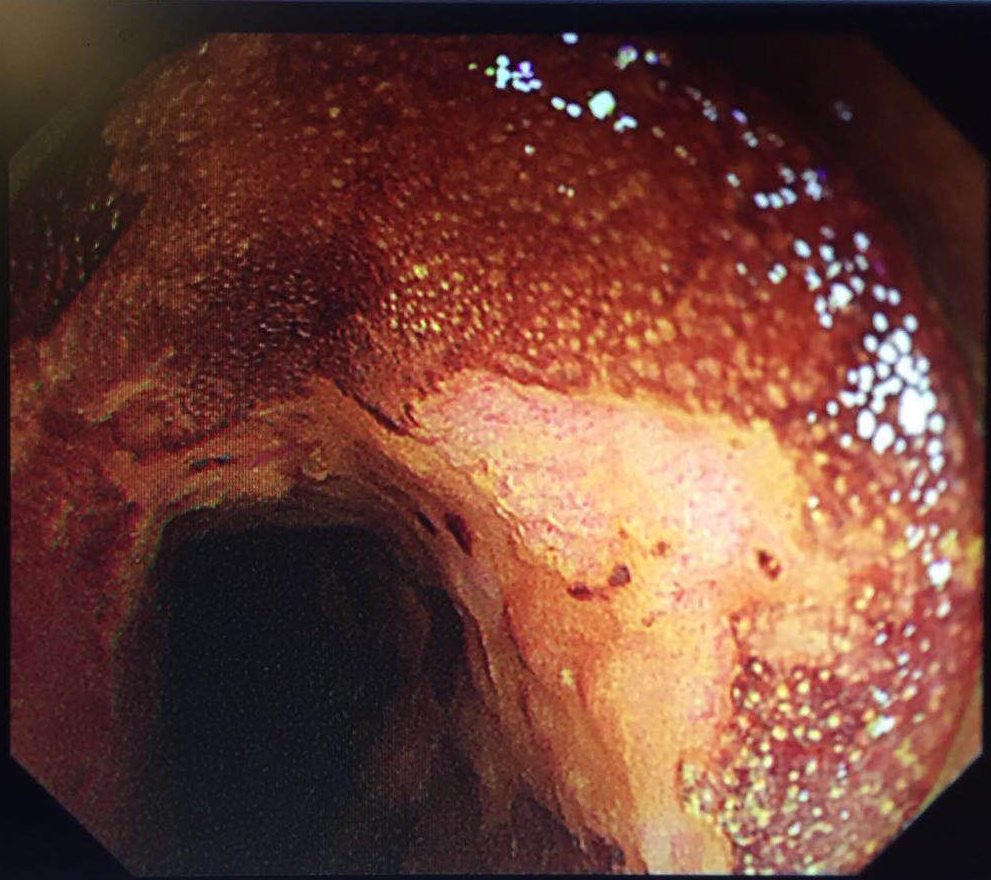

4月20日,第二届北京协和医院—福建省立医院消化内镜合作共建学术会议在北京协和医院召开。我院消化内镜中心梁纬主任带领14人的团队参加会议,邓万银副主任医师作手术演示。浙江大学附属第一医院许国强副院长,北京协和医院消化内科吴晰副教授、冯云路博士分别就《环形超声扫描操作技巧》《纵轴超声扫描技巧》《小探头操作技巧》作主题演讲。

与此同时,北京协和消化疾病及消化内镜国际论坛暨第25届北京协和医院消化疾病与消化内镜研讨会在北京举行,国内外五十余位专家、五百余位代表参会。梁玮主任受邀作手术演示,完美演绎了一例病灶长达200px近环周的高难度早期食管癌“梁式ESD”治疗,向国内外同仁展示出精湛、创新的福建消化内镜技术,赢来阵阵喝彩。